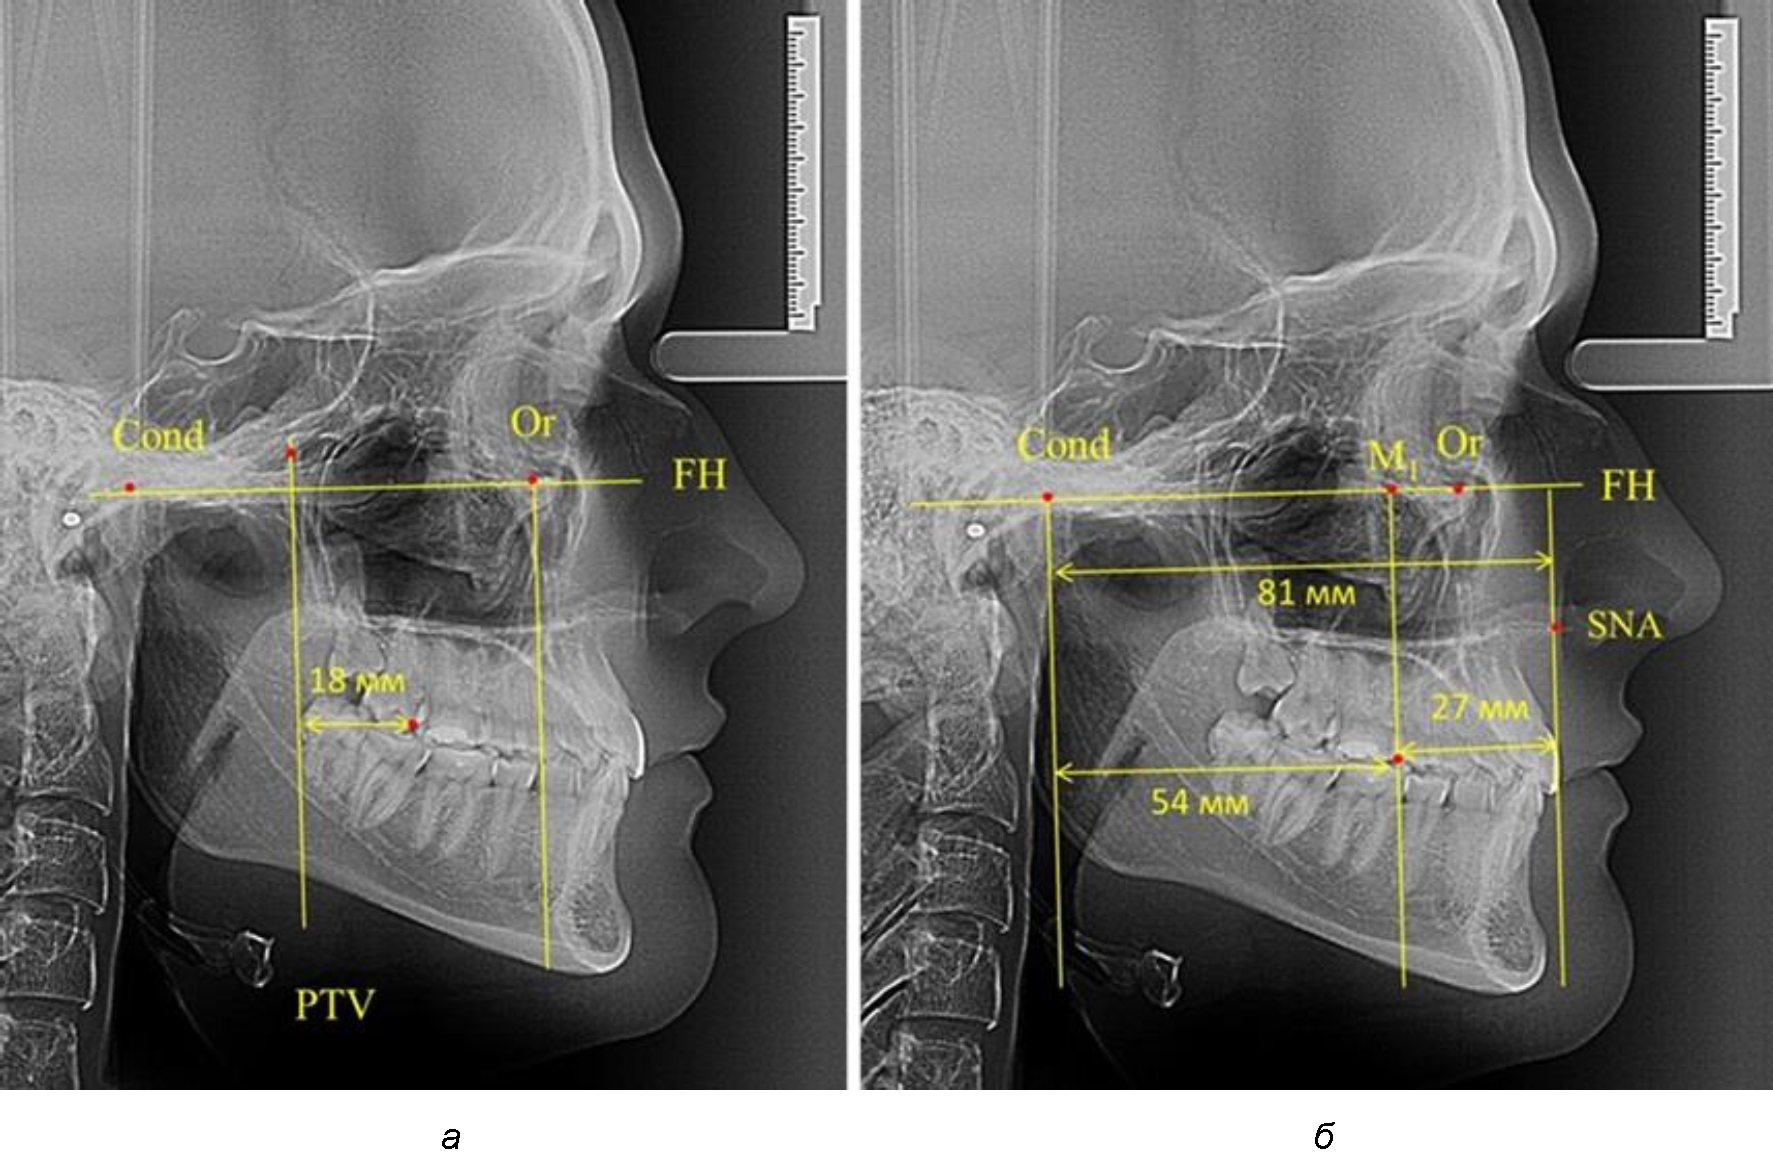

Согласно указанному методу на рентгенограммах проводили Франкфуртскую горизонталь. Учитывая мнения специалистов относительно ориентиров для построения и вариабельность положения наружного слухового прохода, в качестве задней точки использовали верхнюю выпуклость суставной головки нижней челюсти («Cond»). Передняя точка традиционно располагалась на нижнем крае глазницы и определялась как орбитальная точка Or.

Находили положение точки Pt, которая располагалась на пересечении нижнего края круглого отверстия и задней стенки крыловидно-верхнечелюстной щели, и перпендикулярно к Франкфуртской горизонтали проводили крыловидную вертикальную линию, которую принято обозначать как плоскость PTV. Расстояние от крыловидной вертикальной плоскости PTV до дистальной поверхности верхнего первого постоянного моляра определяло его положение, которое, по мнению R. E. McDonald, соответствовало возрасту пациента, увеличенному на 3 мм.

При проведении анализа к Франкфуртской горизонтали проводили передний и задний перпендикуляры. Передний спинальный перпендикуляр проходил через выступающую точку передней носовой ости (spina nasalis anterior – SNA), а задний суставной перпендикуляр опускали из кондилярной точки Cond. Молярный перпендикуляр проводили через медиальную поверхность первого постоянного моляра. Указанная вертикаль отделяла замещающие зубы постоянного прикуса от добавочных зубов (постоянных моляров), что вполне логично для анализа положения первых постоянных моляров в гнатическом комплексе (рис. 1).

Рис. 1. Метод определения положения первых верхних моляров по Ralph E. McDonald (а) и по предложенному методу (б)

Анализ проведенного исследования рентгенограмм показал существенную вариабельность практически всех линейных показателей. У молодых людей с физиологическим прикусом постоянных зубов расстояние от крыловидной вертикальной плоскости PTV до дистальной поверхности верхнего первого постоянного моляра в целом по группе составляло (18,37 ± 3,62) мм. Обращает на себя внимание большая ошибка репрезентативности из-за разницы между максимальными и минимальными значениями.

Среди анализируемых рентгенограмм минимальное значение расстояния по методу R. E. McDonald было 12 мм, а максимальное достигало 25 мм, что, по нашему мнению, обусловлено вариабельностью сагиттального размера гнатического отдела лица.

Среднее расстояние между суставной (кондилярной) и спинальной вертикалями в анализируемой группе составило (89,12 ± 2,8) мм. При этом сагиттальный размер в среднем составлял (58,74 ± 1,57) мм, а передний размер был (30,41 ± 1,02) мм. Несмотря на вариабельность размеров и большую ошибку репрезентативности, относительно стабильным показателем было отношение сагиттального размера гнатического комплекса к заднему отделу, которое составляло в среднем 1,5 ± 0,06.

Таким образом, для прогнозирования оптимального положения первых постоянных моляров наиболее целесообразным методом явилось использование относительного показателя, что подтверждено при анализе рентгенограмм с минимальными и максимальными значениями по методу R. E. McDonald.

Так, при расстоянии от крыловидной вертикальной плоскости PTV до дистальной поверхности верхнего первого постоянного моляра в 13 мм сагиттальный размер гнатического отдела был 82 мм. При этом отношение кондилярно-спинального расстояния к кондилярно-молярному размеру (54,5) было близким к коэффициенту 1,5, что представлено на рис. 2.